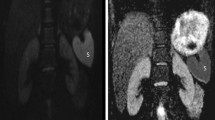

All VCUG images were reviewed by a radiologist (C.M.P., 32 years of experience in abdominal imaging). VUR was graded according to the international classification system developed by the International Reflux Study Committee [15]. All MR images were reviewed by two radiologists (C.H.L., J.W.K., 19 and 3 years of experience in abdominal imaging, respectively) blinded to the VCUG results. The radiologists manually positioned a circular region of interest (ROI) in the renal pelvis on the apparent diffusion coefficient (ADC) maps. The ROI was placed at the same position in the renal pelvis on the ADC and parametric maps by displaying all images in tandem on the PACS monitor, copying the ROI from the ADC maps and pasting it to the parametric maps for D, D* and PF. The circular ROI greater than or equal to 10 mm2 was drawn as close as possible to the center of the renal pelvis. For each ROI, the mean value of each parameter (ADC, D, D* and PF) derived from the pixel-by-pixel analysis was automatically computed. The radiologists measured ADC and IVIM parameters five times at 1-week intervals. The median value of each measurement was used as the representative value. Examples of ADC and IVIM parameter measurement in the renal pelvis are shown in Figs. 2 and 3.

A 3-month-old boy with hydronephrosis in both kidneys on abdominal sonography and MR urography. ADC, D, D* and PF values of both kidneys were measured on the axial ADC map (b) and the parametric maps for D (c), D* (d), and PF (e). PF/D index values of the right and the left kidneys were 8.84 and 5.60, respectively. Because an optimal cut-off value obtained in a ROC curve analysis was 8.7, we predicted that there was VUR only in the right kidney. Actually, VCUG result was concordant with our prediction (a)